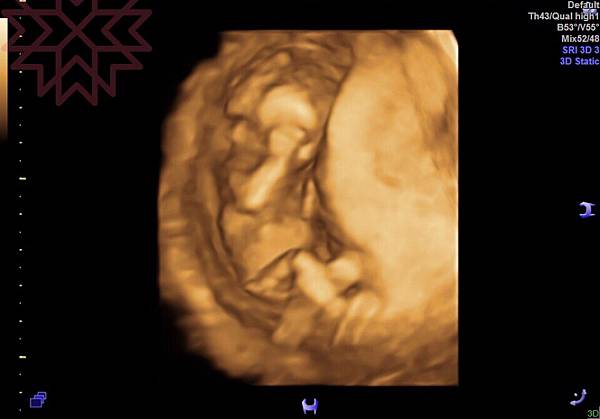

附上檢查後的幾張影像,和一張外星人的3D照。

下面為寶寶今天趴著的特寫,有乖乖長大喔。